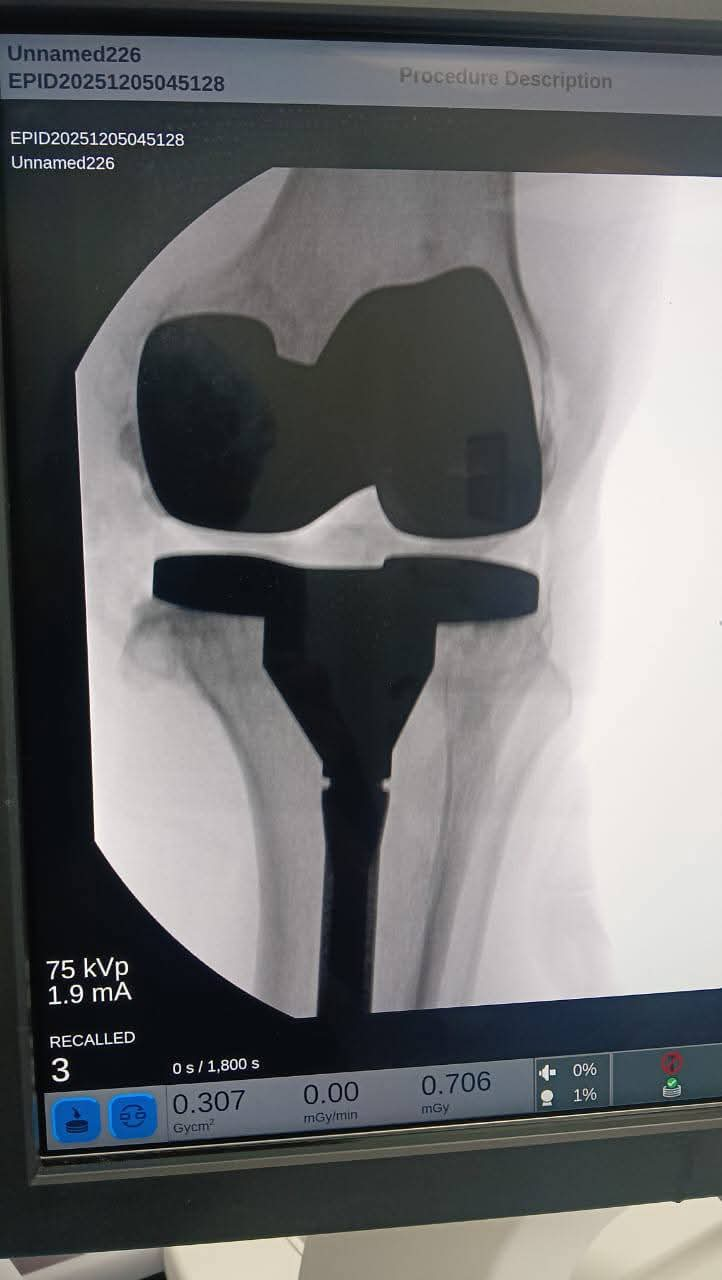

حقق الفريق الطبي بمستشفى القنطرة شرق التابعة لفرع الهيئة العامة للرعاية الصحية في محافظة الإسماعيلية، إنجازًا جديدًا بإجراء عملية دقيقة لاستعدال الركبة وتركيب مفصل ركبة كامل أسمنتي ذي جذع طويل (Long Stem) لمريض يبلغ من العمر 56 عامًا، بعد معاناة طويلة من خشونة متورمة وتشوه شديد بالخارج للركبة اليسرى، وهي من الحالات المتقدمة التي تتطلب مهارة عالية وخطة جراحية دقيقة.

وخلال الجراحة، نجح الفريق في استعدال المحور التشريحي للساق وتصحيح التقوس، ثم تركيب المفصل الصناعي المزود بجذع طويل لضمان الثبات والدعم في الحالات المتقدمة.